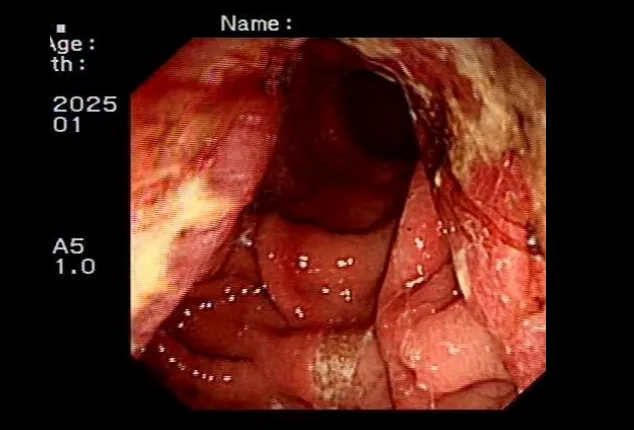

三、胃肠外科:多科协作,攻坚复杂二次手术

胃肠外科面对复杂、高风险的二次肿瘤手术展现出强大实力。一例66岁残胃癌复发患者,11年前曾行胃癌部分切除术,腹腔粘连严重,且合并肺气肿、营养不良等多重问题。胃肠外科牵头组织心内科、麻醉科、呼吸内科、影像科、临床营养科、中医科等进行多学科(MDT)会诊,制定了周详的个体化手术与围手术期管理方案。团队成功为患者实施了高难度的“残胃切除+食管空肠吻合+淋巴结清扫+粘连松解”手术。术后,针对患者出现的血压偏低等情况,心内科与中医科协同干预;临床营养科全程提供阶梯式营养支持。在多学科无缝协作下,患者平稳度过危险期,未发生严重并发症,顺利康复出院。该案例是我院利用多学科(MDT)综合诊疗模式优势处理复杂腹部肿瘤的成功典型案例。